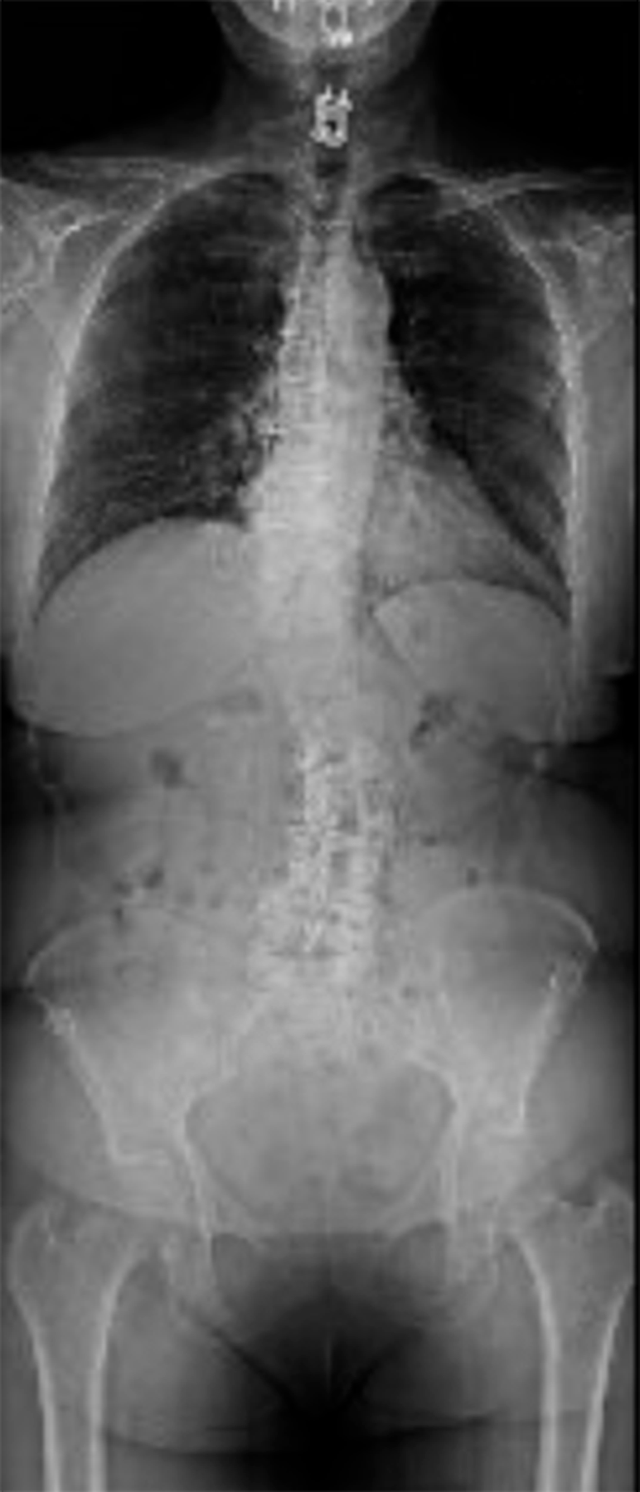

At my first visit, Dr. Shah scared the living daylights out of me. He diagnosed me with severe scoliosis and explained how my spine was twisting around itself. Unlike in more moderate cases, my curvature grew worse when I tried to stand up and go about daily life.

To fix it, I needed a two-day surgery. First the surgical team would open me up from the front and move my organs to prep my spine. The following day, they would measure all my nerve signals in real time, widening their pathways and then placing various rods and screws into my discs and pelvis—all without pinching off additional nerve channels. Dr. Shah explained the risks, including a great potential for blood loss. But if the surgery was successful, he said, I’d be pain-free.